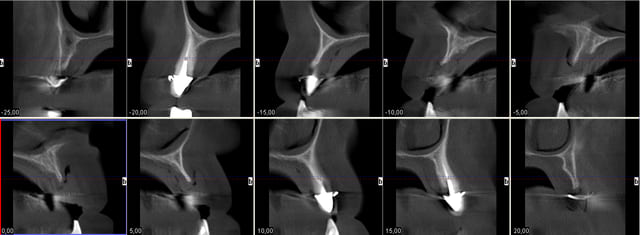

Cas promis... à dentiste 57 et à growler... le voici

Pour Pluton aussi ;-))))

Bon je cesse la liste sinon je vais créer un ordre de préséance entre vous , ordre malvenu sans doute ;-)))

Pp

1. C est toi qui es malhabile... Rien de plus simple : tu mets ttes tes vis ds la puits, tu les recouvres d homéoplasmine pour les empêcher de tomber hors des puits, tu poses en bouche et tu passes ton tournevis ds homéoplasmine pour visser Très simple et très efficace :-))))

2. Effectivemeznt les plaques zygomatiques ont des émergences palatines mais au définitif j ai ôté les piliers prlongateurs de 3.5 mm et du coup même si sortie palatine plus aucun "débordement" du puits de vissage en dehors de l arcade...

3.Ca fait 18 mois que les implants sont en charge donc tu as déjà une idée mais de manière générale ça fonctionne aussi bien qu pilotis à la mandibule... Un petit coup de waterpik léger et qques bains de bouches suffisent à entretenir tout ça correctement

De tte façon si tu fais pas ce que je viens de faire, tu es cuit pour deux sinus-lifts ( dont la patiente ne voulait pas !!!!! )et encore tu n auras aucun implant au delà des 4 voire des 3 donc un terrible porte-à-faux devant... Sinon tu dois ajouter un Lefort pour interposer un bloc au niveau incisif... Elle refuse encore plus le Lefort que les sinus-lifts

PS Cette résorption est le résultat du port d un amovible complet de 30 ans à 63 ans ...